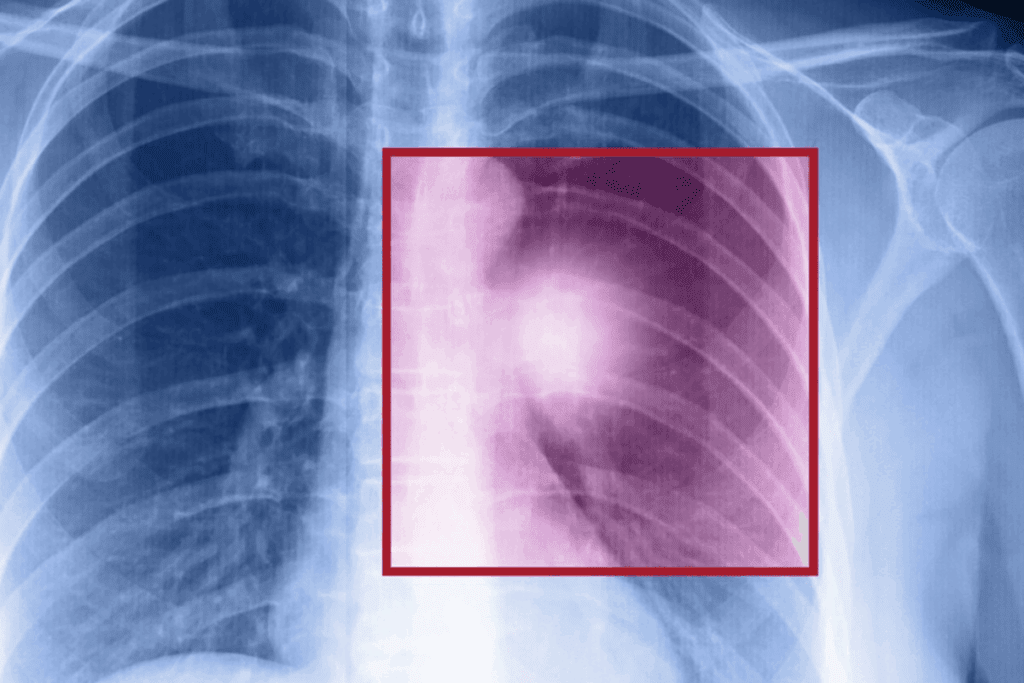

Do They Break Ribs for Thoracotomy? The Truth Explained

It’s important for patients to know how ribs are handled during thoracotomy. This surgery opens up the chest cavity. We’ll look at the methods used and how they affect the ribs.

Break Ribs for Thoracotomy: Myths vs. Reality

Many people think thoracotomy means breaking ribs. But is this true? This surgery to open the chest is often misunderstood. We want to clear up these myths and share facts to ease worries.

What Actually Happens to Ribs During Surgery

During thoracotomy, surgeons use different methods to open the chest. They might spread the ribs, cut a rib, or use a method that hurts the ribs less. The method chosen depends on the patient’s needs and the surgeon’s expertise.

A study found that the surgery method greatly affects recovery and long-term health. This shows why it’s key to know the details of the procedure.

Evidence-Based Outcomes for Rib Integrity

Research shows that modern thoracotomy techniques protect the ribs well. Most patients have good recovery, with manageable pain and little long-term rib damage.

A key finding is that avoiding rib damage leads to fewer complications. A study found that patients with less rib damage had better recovery and fewer problems after surgery.

“The goal of modern thoracic surgery is to achieve the necessary surgical exposure while minimizing trauma to the chest wall and preserving respiratory function.”

Knowing the truth about thoracotomy and its effects on ribs helps patients prepare for surgery and recovery.